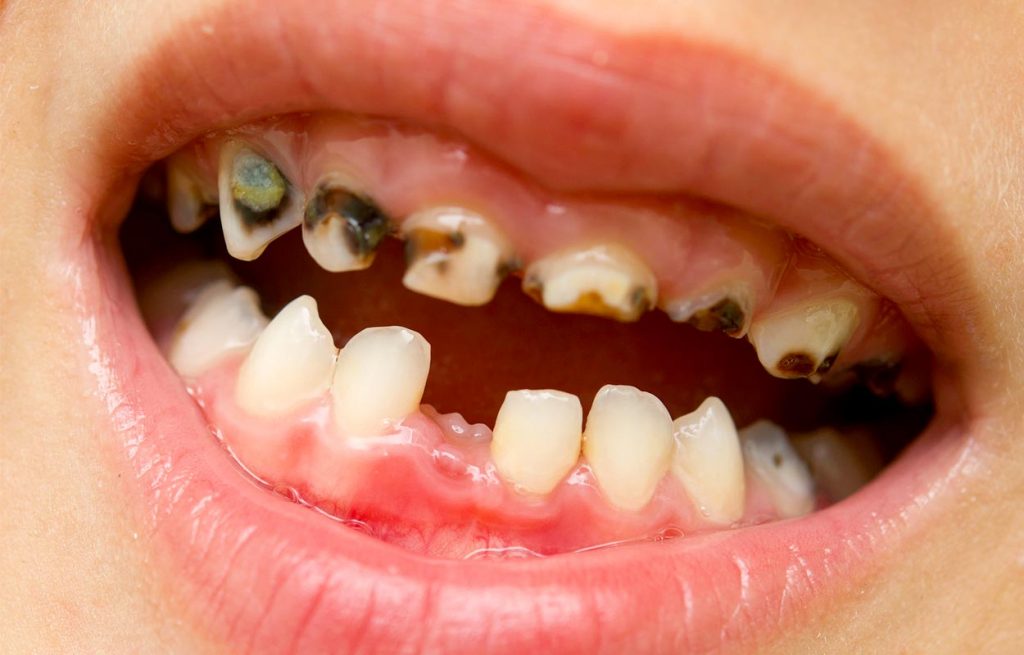

Kai kurių šaltinių duomenimis, maždaug nuo 2012 m. ikimokyklinio amžiaus vaikai su pažeistais dantų ėduonies, arba karieso, dantimis, sudaro apie 90 %, ir šia bloga statistika Lietuva smarkiai lenkia ir ES vidurkį, ir kitas šalis. Pvz., Švedijoje tokio pat amžiaus vaikų su pažeistais dantimis yra tik apie 10%.

Apie 75 % trimečių vaikų dantys jau yra pažeisti dantų ėduonies, arba karieso, o šešiamečių vaikų tarpe dantų ėduonis paplitęs dar labiau – iki 94%.

Paauglių dantų situacija ne ką geresnė – apie 85 % 12 m. vaikų yra su karieso pažeistais dantimis, o penkiolikmečių, išsaugojusių sveikus nuolatinius dantis, galima sakyti, pasitaiko atskiri atvejai.

Lai nešokiruoja skaitytojų šio straipsnio nuotraukos – jos ne iš siaubo filmo. Tai – realybė. Taip „patraukliai“ atrodyti, save žaloti ir savo gyvybę pasmerkti fiziniam, moraliniam bei psichologiniam skausmui pasirenkama laisva valia. Ko trūksta žmogui, kad apsispręstų kvaišalais naikinti savo gyvenimą? Gal informacijos apie kvaišalais naikinamus žmonių gyvenimus ir žmogiškąją išvaizdą, kurios neatsiejama dalis yra […]

Dantų ėduonis yra dažniausia vaikų liga išsivysčiusiose šalyse. Vidutiniškai apie 40 % vaikų dantų ėduonis prasideda dar ikimokykliniame amžiuje. Vaikų dantų ėduonis yra rimta problema, nes dantų ligos yra betarpiškai susijusios su sveikata apskritai: didina cukraligės, širdies ligų ir kt. riziką. Dėl dantų ėduonies dantų skausmą kenčiantiems vaikams natūraliai tenka ir dažniau praleisti pamokas, prastėja […]